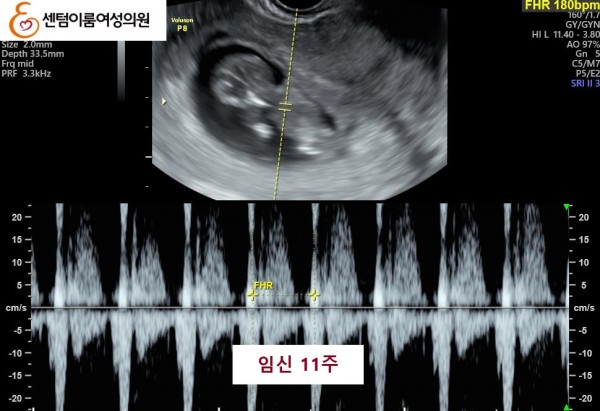

2024.12월 본원 내원 전 타병원에서 다수의 시술 경험이 있으셨습니다.

40세 이상 고령 연령은 염색체 비정상 난자 비율이 높아 고난도 난임의 대표적인 사례입니다.

꾸준한 식생활 개선과 약물 치료를 받으시고 임신에 성공 하셨습니다.